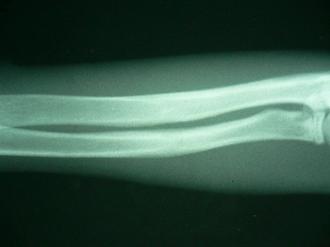

やんちゃ盛りの「いん」は、他の仲間と大騒ぎの毎日です。この度、仲間と遊んでいる最中に腰の高さから落ちたそうです。それ以降、足を痛そうにしているとの主訴で来院されました。病院で早速レントゲンを撮影すると、右の写真の通り、右前肢2本(前肢は、二本の骨で構成されます)の骨折が見られました!みずみずしい木の枝を折ったときの様相を呈するこの不完全骨折を「若木骨折」と呼びます。